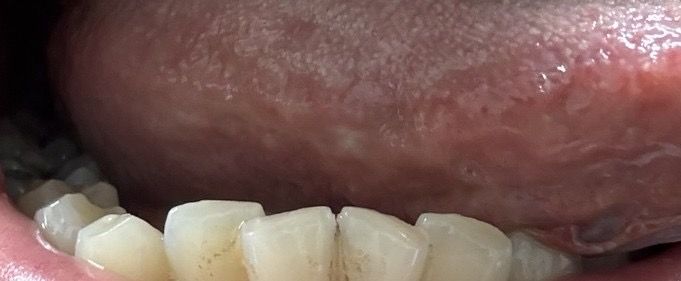

저번주 금요일에 자고일어났더니 혀에 뭐가 났는데요

저번주 금요일에 자다가 혀에 통증이생겼는데

깨문건지 모르겠는데 엄청 건조했어요 입안이

일어나서 확인해보니 첫번째 사진처럼 되어있더라구요

그리고 오늘 확인해보니까 두번째사진처럼

아직 하얗게 남아있는데

낫고있는건지 아니면 병원을 가봐야되는건지

답변 부탁드릴게요!!

• 2번 째 사진

혀에 생긴 문제로 걱정이 많으시겠네요. 사진으로만 봐서는 정확한 판단이 어렵지만, 하얗게 남아있는 것을 보면 염증 반응이거나 구강 건조로 인한 변화일 가능성이 있습니다. 혀는 예민한 부위라 작은 자극에도 쉽게 염증이 생길 수 있고, 수면 중 입안이 건조해지면 더욱 악화될 수 있어요.

사진을 보면 혀 점막에 외부 충격이 가해지면 일부 손상이 발생하였고 이후 염증 반응이 일어나면서 국소 설염이 발생한 것으로 보입니다. 이러한 설염은 특별한 치료 없이도 일반적으로 1-2주 이내에 호전이 되며 흡연자라면 흡연을 중단하는 것이 도움이 됩니다. 만약 1~2주 이후에도 호전이 없거나 궤양의 형태로 변한다면 이비인후과 진료를 보시는 것이 도움이 되니 고려해 보시기 바랍니다. 답변이 도움이 되었기를 바랍니다.